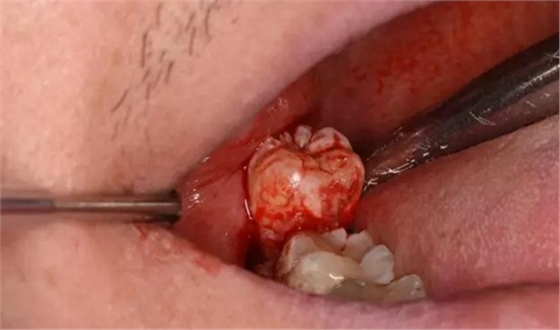

圖10.普通牙挺放置在48牙冠的近中面與牙槽嵴之間,先推后挺。

圖11.分別在近中和頰側(cè)反復(fù)用挺

圖12.最后使用挺力和撬力,使48從合向脫位